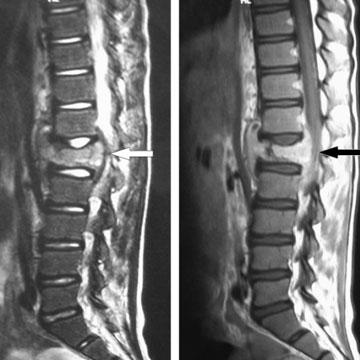

Tuberculosis

Degenerative